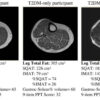

Visualizing Declining Muscle Quality

T1 cross-sectional images of the legs of a control, a patient with Type 2 diabetes (T2DM), and a Type 2 diabetes patient with peripheral neuropathy (T2DMPN). These images exemplify the progression of obesity (control) to T2DMPN and the accompanying loss of subcutaneous adipose tissue (SQAT), accumulation of leg intermuscular adipose tissue (IMAT), loss of muscle volume (gastroc-scoleus% vol.), and...